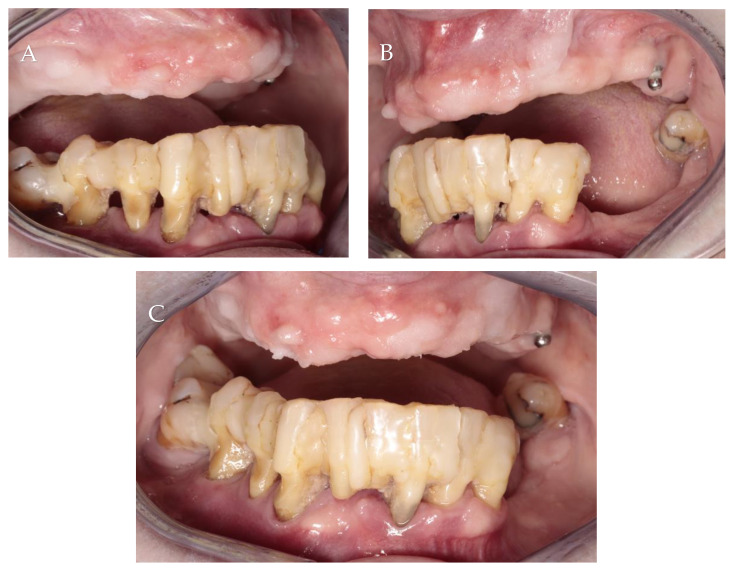

Initial intraoral photographs: (A) right lateral view; (B) left lateral view; (C) frontal view.